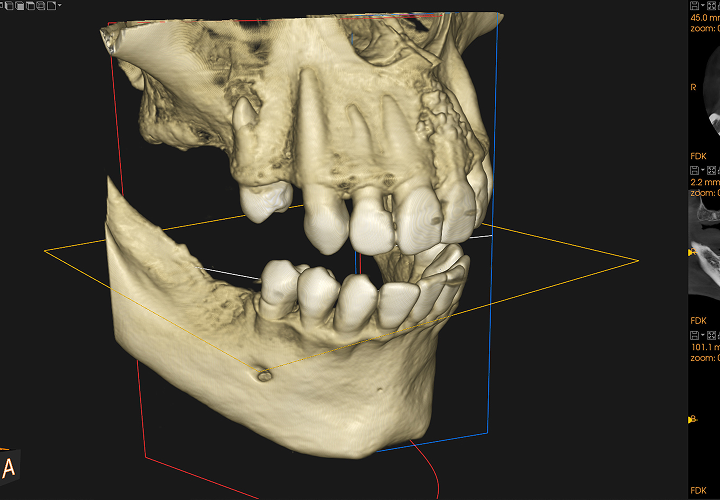

CT・セファロによる骨格診断

矯正治療において、正確な骨格診断は治療に欠かせません。当院では、CTスキャンとセファロ(頭部X線規格写真)を用いて、患者さまの骨格や歯の位置関係を詳細に分析します。em>CTスキャンは歯や骨の立体的な画像を提供し、骨の構造や形態を正確に把握できます。一方、セファロは顔面の骨の角度や歯の配列を計測し、矯正治療における骨格のズレを把握します。これらのデータをもとに、最適な治療計画を立案し、より精度の高い矯正を実現します。

3Dスキャナー(iTero、プライムスキャン)

当院では、診断の設備として最新の3Dスキャナー(iTero、プライムスキャン)を導入しています。患者さまの歯並びを高精度でデジタルスキャンし、3D画像として確認しています。この技術により、従来の型取りに伴う不快感を軽減し、短時間で正確なデータが取得できます。さらに、治療計画や矯正装置の作成も、精密なデジタルデータをもとに行うため、治療の効率性と精度が大幅に向上します。患者さまにとって、より快適で確実な治療が提供できる環境が整っています。